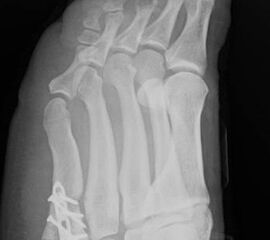

Abb. 12a: Typ III Deformität präoperativ im belasteten dp Röntgenbild.

Abb. 12b: Dorsoplantare Röntgenkontrolle nach medial schließender Osteotomie mit Schraubenosteosynthese.

Abb. 12c: Schrägaufnahme nach medial schließender Osteotomie mit Schraubenosteosynthese.

Abb. 12d: Seitliche Aufnahme nach medial schließender Osteotomie mit Schraubenosteosynthese.